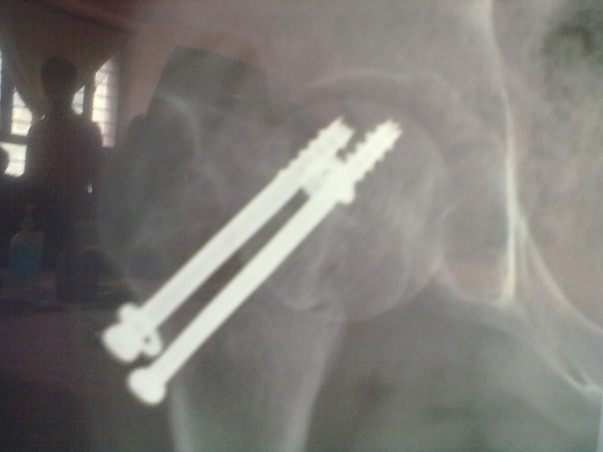

Spinal block was used in the procedure. Prone position on fracture table with radiolucent top was used. Fracture site was exposed through posterior approach and sclerosed margins of the fragments were freshened. Fracture was reduced with appropriate neck shaft angle and fixed with Moors pin/ knowels pin or 4 mm /7mm partially threaded cancellous screws. Any rotation or tilt was corrected. The fixation was augmented with quadratus femoris muscle pedicle bone graft harvested from intertochateric crest area with a bone pedicle of length 2 cm, width 1 cm and depth 1 cm. The graft was secured to the proximal femoral head fragment with 3.5mm cortical screw or 4mm cannulated cancellous screw. Soft tissue closure was done over drain.

Patients were followed up at 2 weeks, 4 weeks, 6 weeks, 8weeksk, regularly at 6 week interval for next 6 month and then at three month interval up to two year. Radiographic analysis was performed at each follow up with special attention to extent of callus formation, alignment of fragments and hard ware integrity.